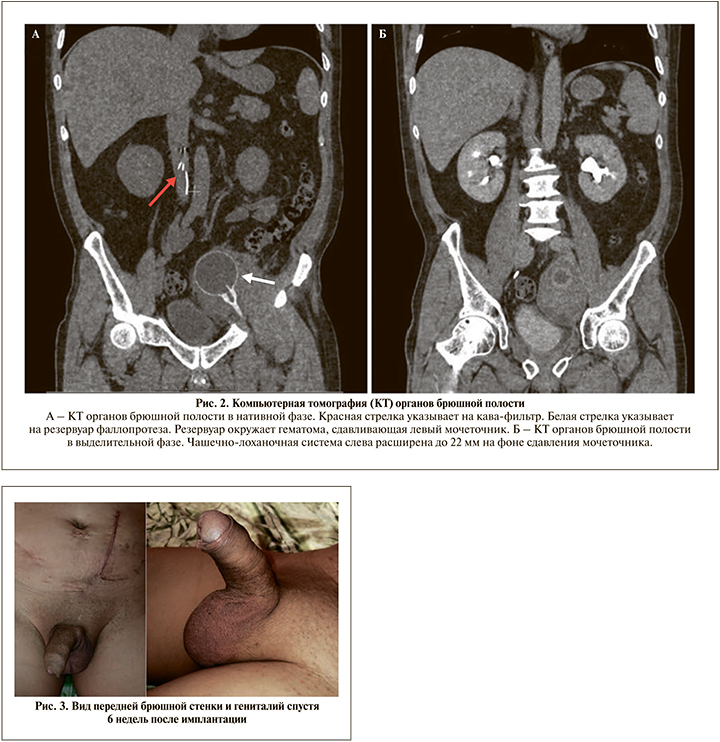

Спустя месяц пациент вновь обратился в клинику с жалобами на общую слабость, тошноту, повышение температуры тела до 39,2оС. При осмотре явных признаков перипротезной инфекции обнаружено не было. При дообследовании выявлено расширение чашечно-лоханочной системы слева и верхней и средней третей левого мочеточника (рис. 2). Клиническая картина расценена как обструктивный пиелонефрит слева. Причиной обструкции послужила гематома, образовавшаяся вокруг баллона фаллопротеза. Пациенту выполнена установка внутреннего мочеточникового стента слева и назначена антибактериальная терапия.

Фаллопротез был активирован через 6 нед. после имплантации (рис. 3). Стоит отметить, что вышеописанные события не повлияли на функционирование устройства и спустя 8 мес. после имплантации пациент остался доволен результатом.